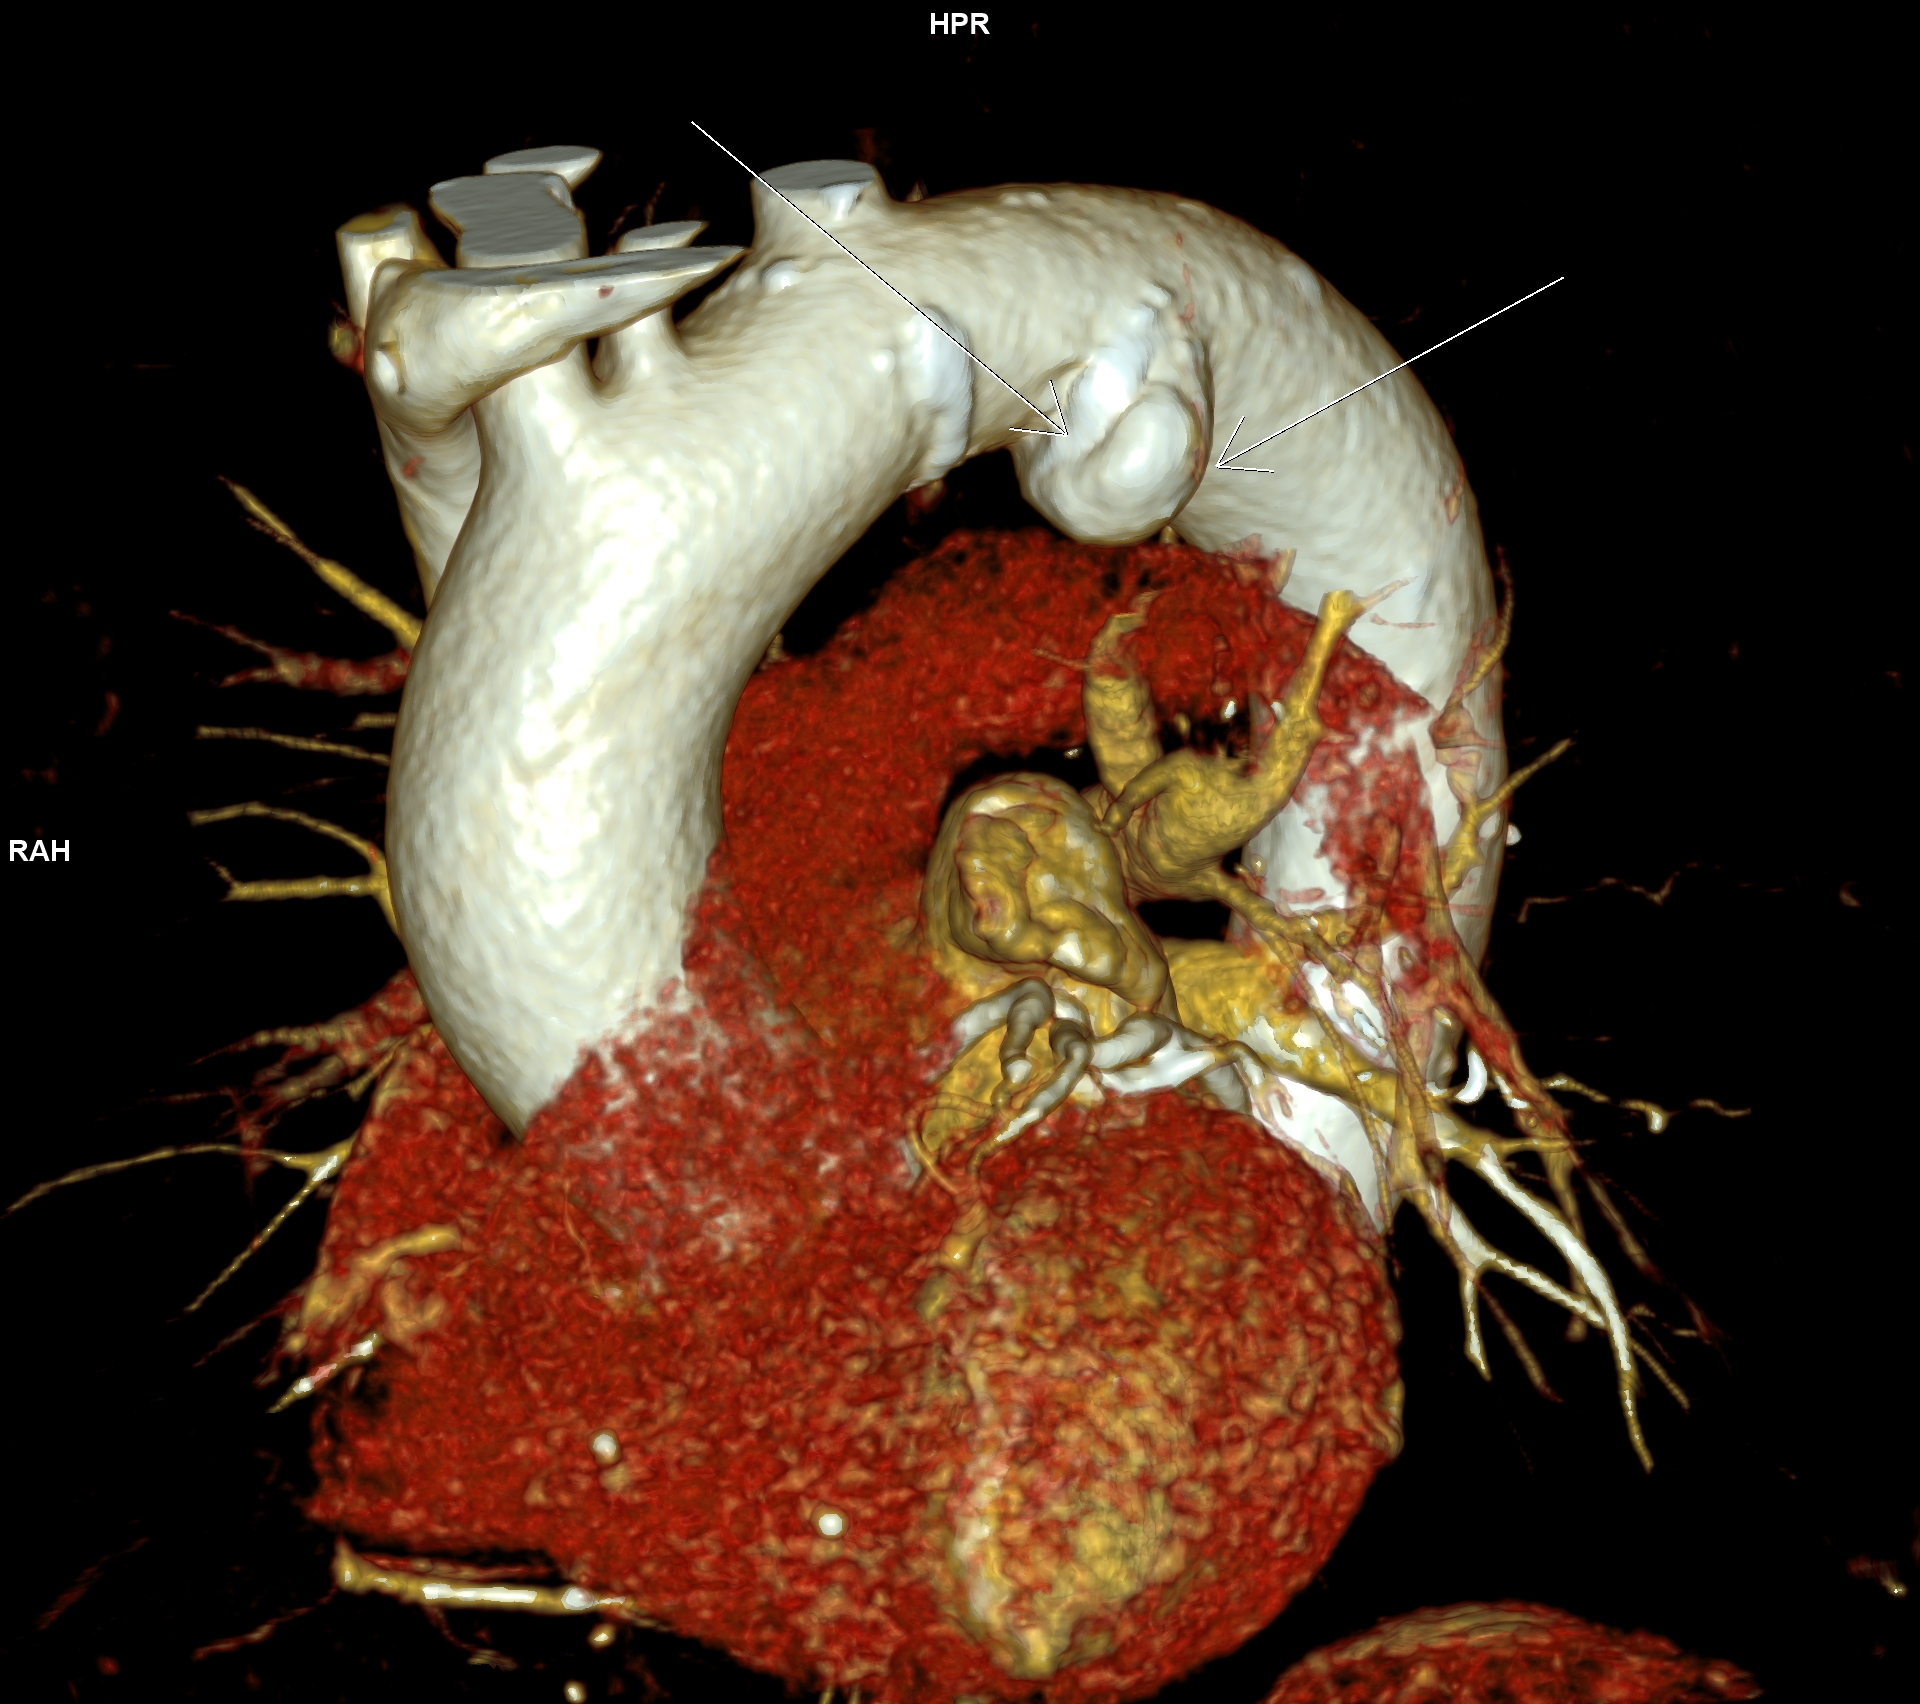

Figurile 1 si 2: reconstrucție multiplanară din achiziție angio în timp arterial – aorta toracică

Figurile 3, 4, 5 si 6: reconstrucție volumică din achiziție angio în timp arterial – aorta toracică

Discuţie caz nr 102: Ductul arterial este o structura de by-pass între aorta descendentă și trunchiul de arteră pulmonară care funcționează în viață intrauterină deoarece plămânii nu sunt aerați; în mod normal se închide în primele zile după naștere. Imaginile prezentate arată că ductul arterial este închis însă se evidențiază creșterea calibrului unei reminiscențe a ductului arterial la deschiderea în aorta descendentă.

DE LUAT ACASĂ!!! Inserția ductului arterial în aorta descendentă toracică este util să fie cunoscută deoarece dacă avem canal arterial permeabil acesta poate fi de dimensiuni mici și poate să nu cauzeze probleme semnificative rămânând nedetectat – practic descoperire întâmplătoare.